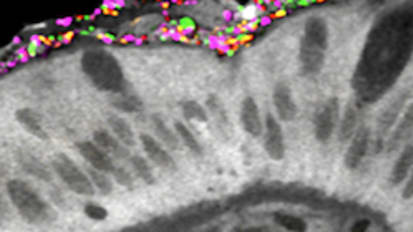

3D Tissue Models Offer Window into How Gut Cells Fight Infection

Nicholas Zachos and his team are the first to cultivate a primary human macrophage-enteroid system, which allows researchers to see, in real time, how the gut fights against infection.